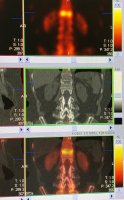

Przykładowe obrazy scyntygraficzne uzyskiwane w naszym Zakładzie Medycyny Nuklearnej: